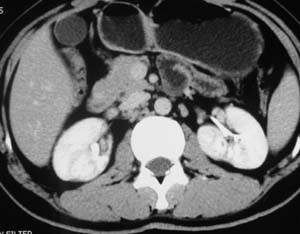

以下是引用子期在2010-3-19 20:47:00的发言:[br]血管畸形的ct增强应该有明显强化,本例并不相符合。本例双肾局部的略低密度影,累及肾盂,局部皮质明显变薄、内陷,增强扫描有轻度的强化,应考虑为炎性病变,患者为年轻男性,累及双肾的感染以结核较常见,可以没有明显的临床症状,尿中有时候也并不能查出什么;肾脓肿常有明显感染中毒症状,本例不符,另外一般的肾盂肾炎或肾小球肾炎通过小便就可确诊,其它还不能排除的是黄色肉芽肿性肾盂肾炎,然而单凭ct一般也很难鉴别。